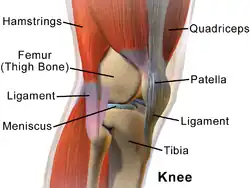

Knee

The knee joint joins the thigh with the leg and consists of the tibiofemoral articulation(one between the femur and tibia) and the patellofemoral articulation(one between the femur and patella)[4].